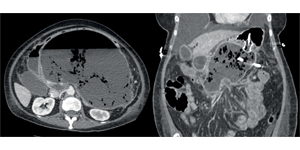

- Панкреонекроз: 1) гостре некротичне накопичення: некапсульований гетерогенний неліквіфікований вміст; 2) обмежений некроз: інкапсульований гетерогенний неліквіфікований вміст. За останнє десятиріччя відбулася значна еволюція у підходах до лікування пацієнтів із панкреонекрозом — із переходом від агресивного хірургічного втручання за допомогою відкритої некректомії до мінімально інвазивного втручання, яке починається із черезшкірного дренування. Ряд випадків продемонстрував, що стерильний некроз може вирішитися без втручань. Мінімально інвазивні підходи до лікування панкреонекрозу включають черезшкірне дренування, ретроперитонеальну санацію, лапароскопічну санацію, черезшкірне трансгастральне дренування або будь-яку комбінацію цих методів.

- Геморагії — кровотечі, найчастіше спричинені ерозією селезінкової чи гастродуоденальної артерії та інших судин, розміщених поряд із підшлунковою залозою. Комп’ютерна томографія з ангіографією підтвердить діагноз геморагічного панкреатиту.